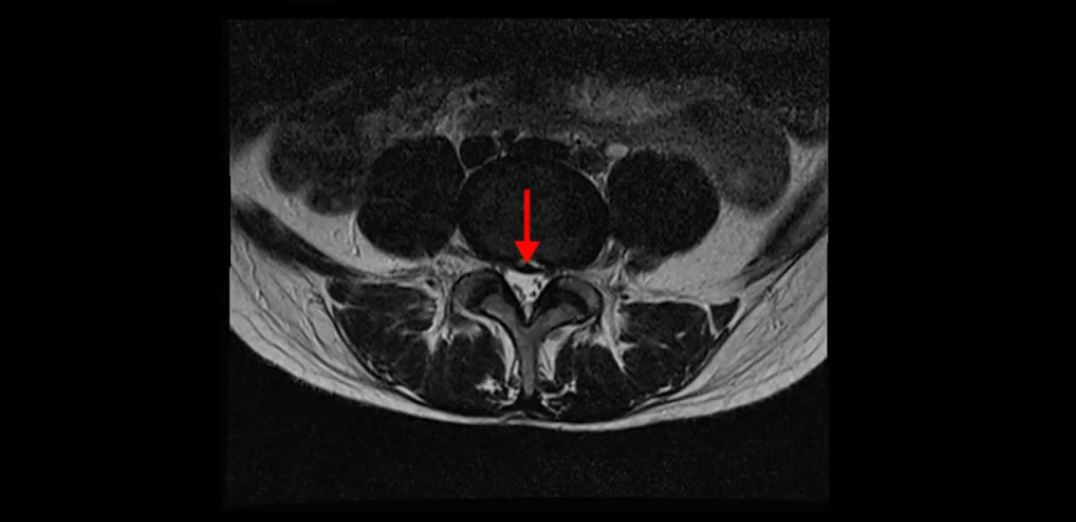

우선 이분의 MRI를 보고 먼저 설명을 드린 후 이런 환자분들의 통증의 원인은 무엇인지, 그리고 치료는 어떻게 해야 하는지 자세히 설명 드리겠습니다.

이분 MRI를 보시면 두 마디의 퇴행성디스크가 있습니다. 그리고 디스크가 조금씩 밀려 나와 있고요. 그런데 디스크 탈출 정도는 두 마디 다 심하지 않습니다. 4번 5번에는 디스크 탈출이 약간 있고,

척추관협착도 약간 진행이 되고 있고요.

5번 1번은 디스크 탈출이 가운데 쪽으로 살짝 있습니다.

또한 양쪽 신경 가지가 빠져나가는 추간공은 매우 넓은 상태입니다.

중요한 것은 이 정도 경미한 탈출과 협착으로는 양쪽 다리가 저리고 아플 수가 없습니다.